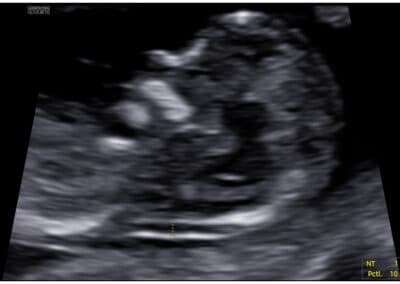

Vyšetření nosní kůstky

věku maminky stáří budoucího miminka srdeční frekvence u miminka velikosti NT (nuchální translucence, respektive šíjového projasnění, tzn. znamená změření množství tekutiny nahromaděné v podkoží v oblasti šíje miminka) (velikost „nuchální translucence“) koncentraci dvou hormonů v krvi maminky (free-ß-hCG & PAPP-A) přítomnosti/chybění nosní kůstky plodu normálního nebo abnormálního průtoku krve (výskytu trikuspidální regurgitace) na trojcípé srdeční chlopni miminka normálního nebo abnormálního průtoku (zvýšené hodnoty PI, tzn. indexu pulzatility) v ductus venosus miminka